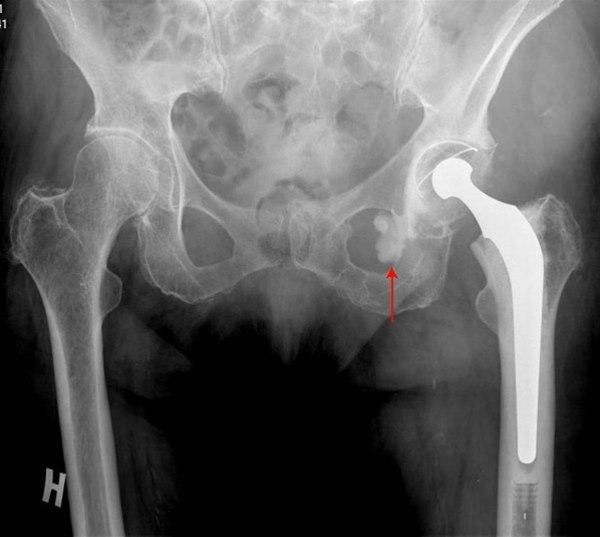

Sementert Charnley totalprotese i venstre hofte

Sementlekkasje medialt (pil)